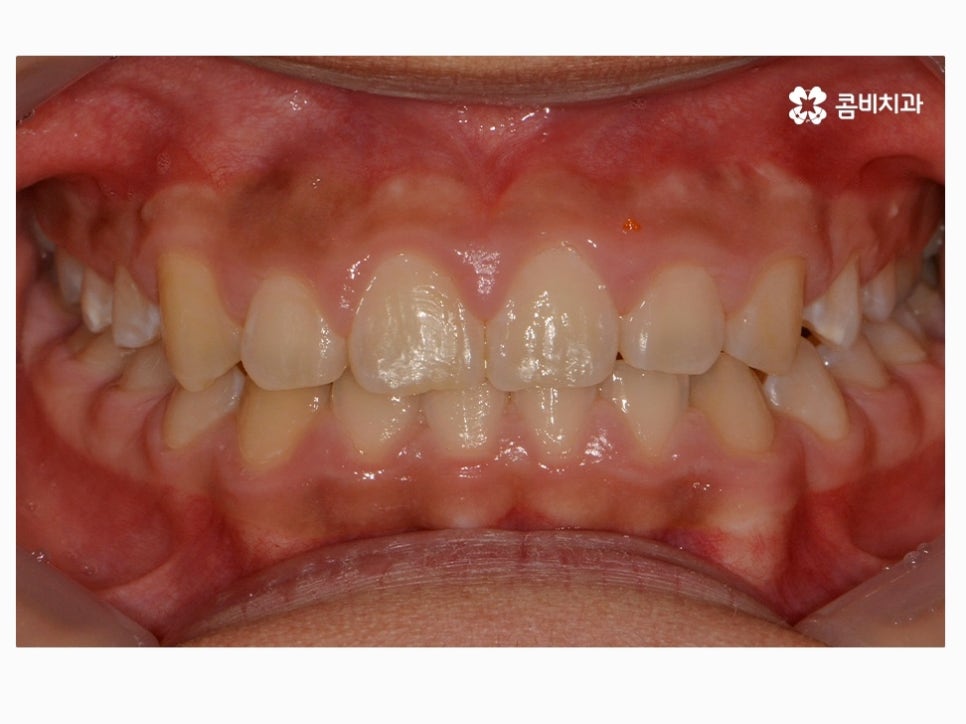

과개교합은 부정교합의 종류 중 하나라고 할 수 있으며

윗니가 아랫니를 정상보다 많이 덮고 있는 형태로 흔히 과개교합 혹은

피개교합으로도 불리고 있어요.

보통 윗니가 과도하게 돌출되어 있거나 치아의 크기가 큰 경우,

아랫니가 과하게 안쪽으로 들어가 있는 경우, 선천적으로 골격성 부정교합에

해당되거나, 이갈이 등 어금니에 과하게 힘이 가해지면서

마모되거나 치관의 길이가 짧아진 경우에

윗니가 아랫니를 덮고 있는 형태를 하게 될 수 있는데요.